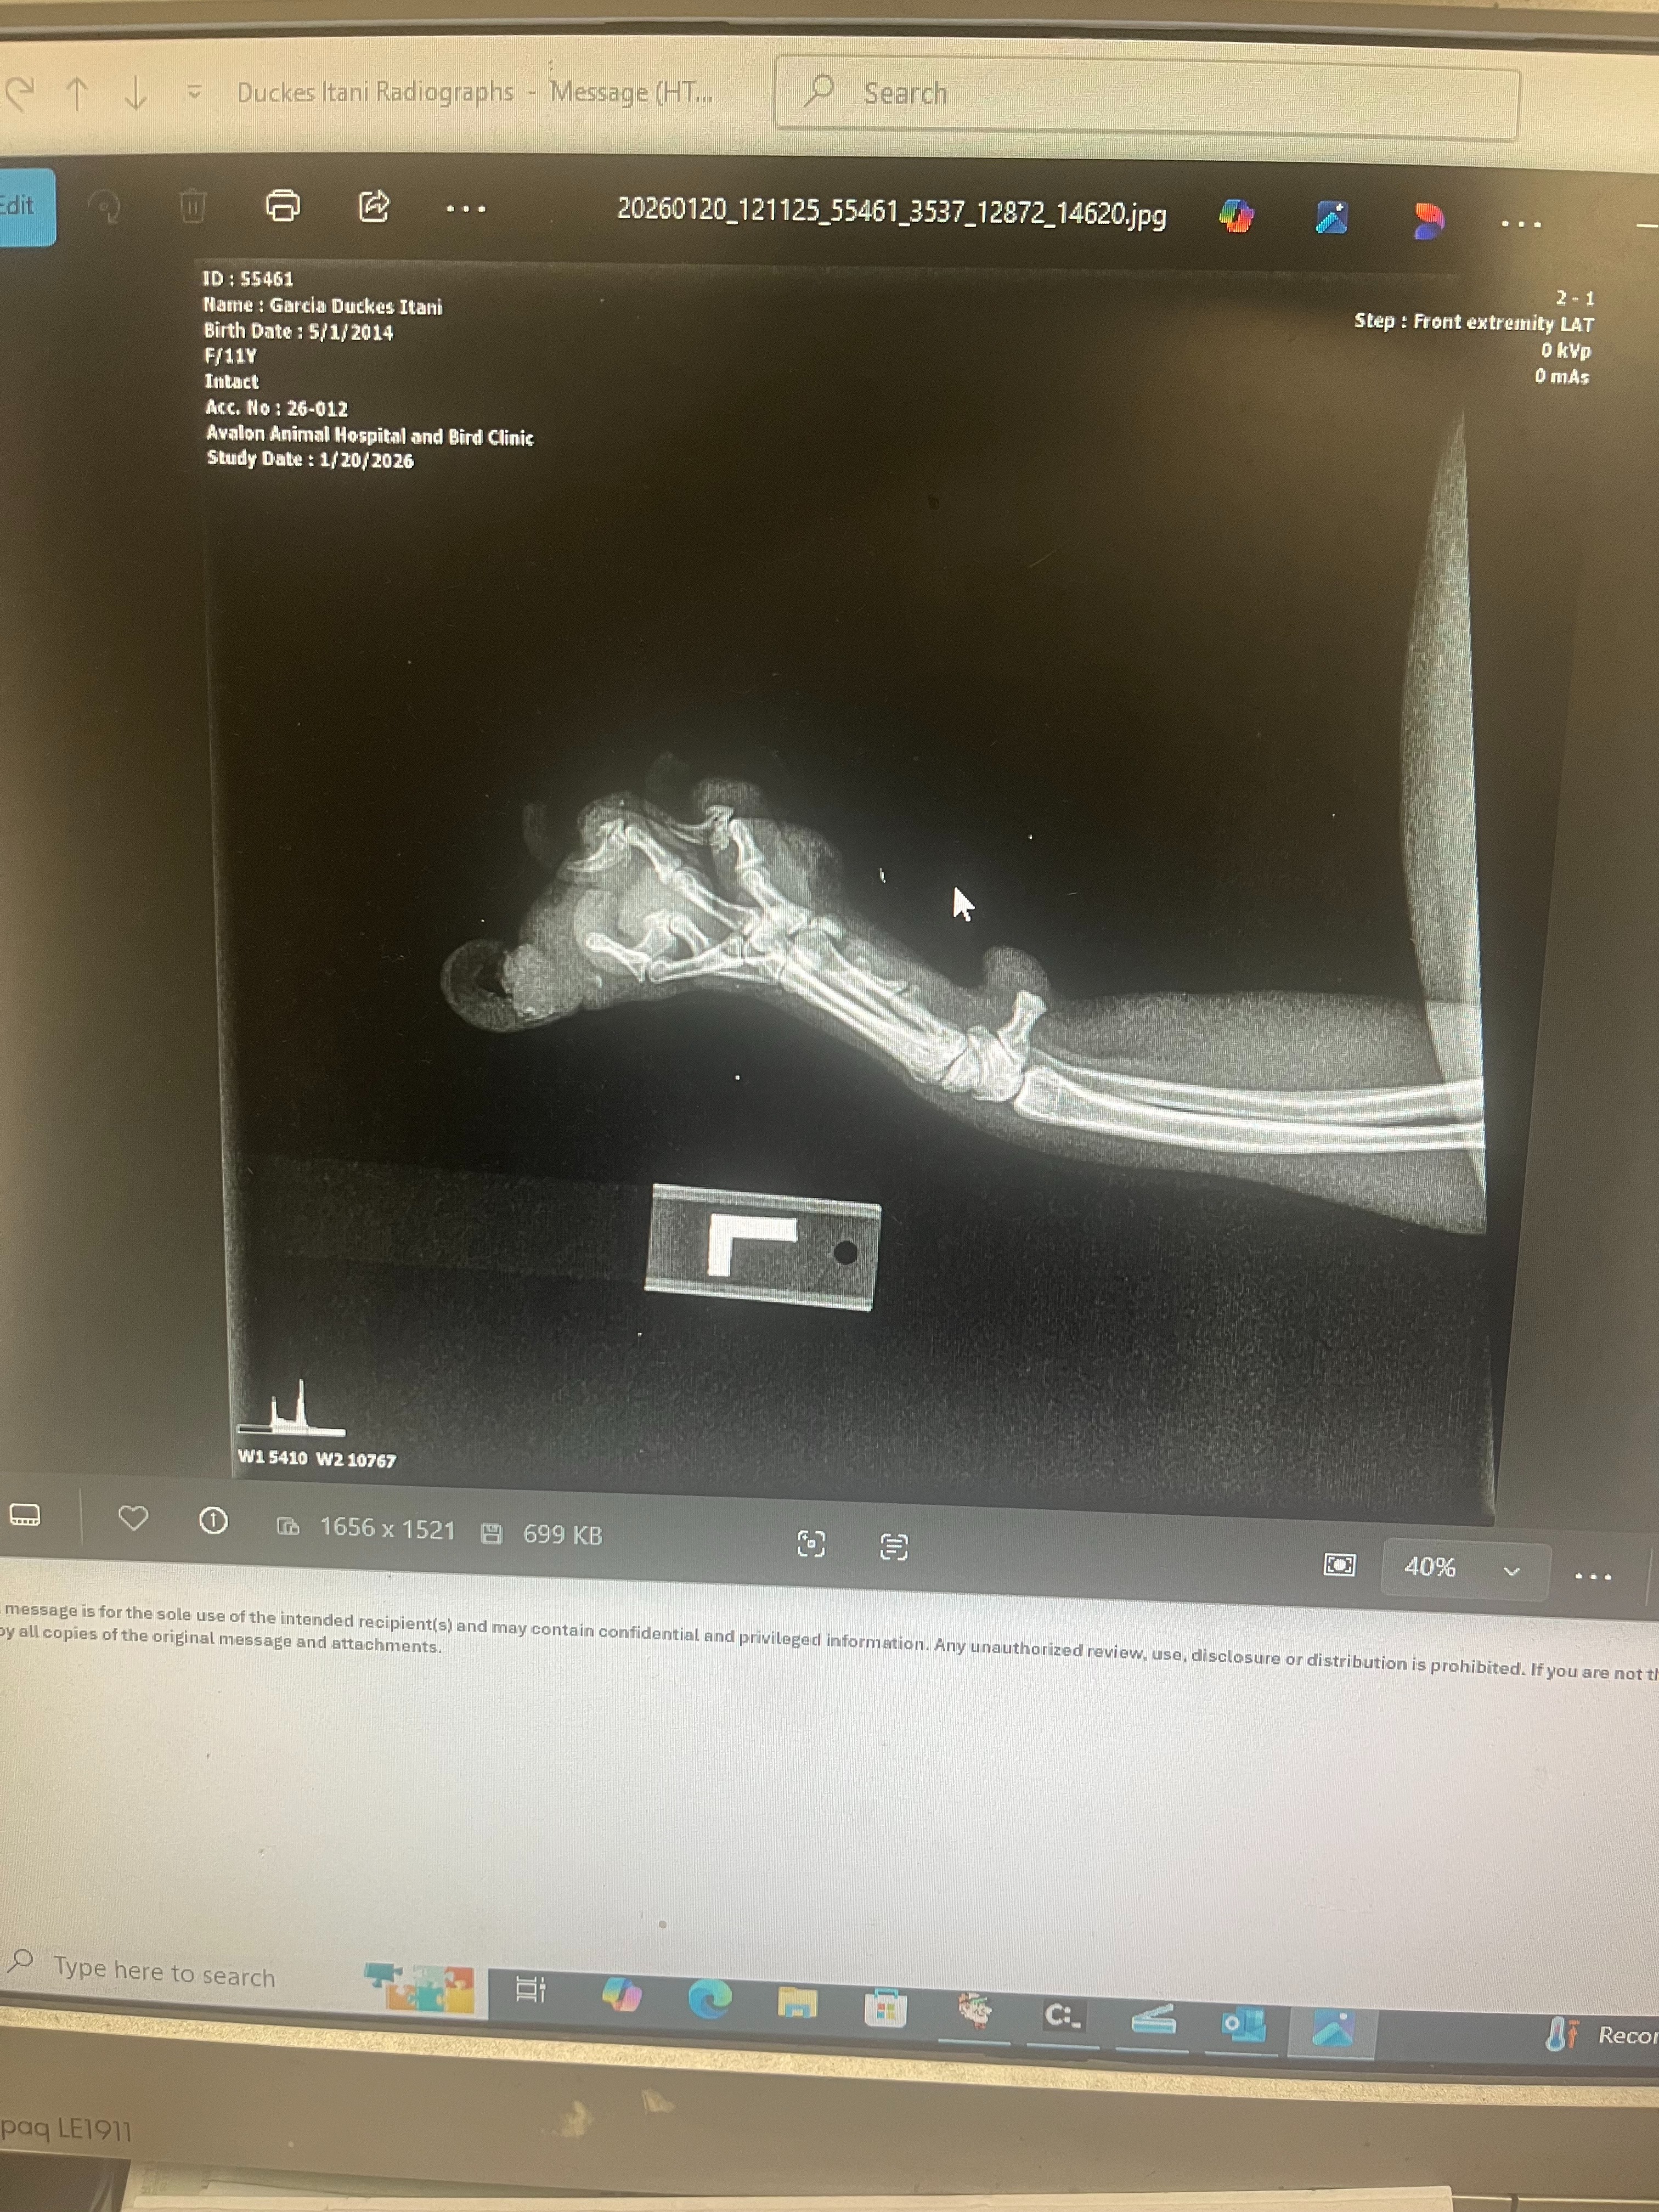

Hello, My family and I are starting this go fund me to try to save our dog. This is Duke He’s 12 years old and has been our loyal companion for so long. He’s currently growing a tumor on his paw. We’ve already had it examined and treated, which was very expensive, and now he needs surgery to fully take care of it.

Hi, I’m Duke I’m 12 years old and my paw has a tumor that needs surgery. My human has already done so much for me, and now we’re asking for a little help.